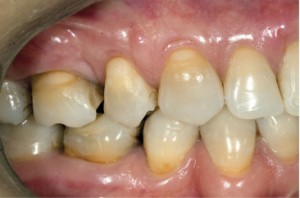

| Pacjentka w wieku 40 lat przed leczeniem. Mnogie (wysokie i szerokie) recesje dziąsła, ryc. 1 | Pacjentka w wieku 40 lat przed leczeniem. Mnogie (wysokie i szerokie) recesje dziąsła, ryc. 2 | |

| Pacjentka w wieku 40 lat przed leczeniem. Mnogie (wysokie i szerokie) recesje dziąsła, ryc. 3 | ||